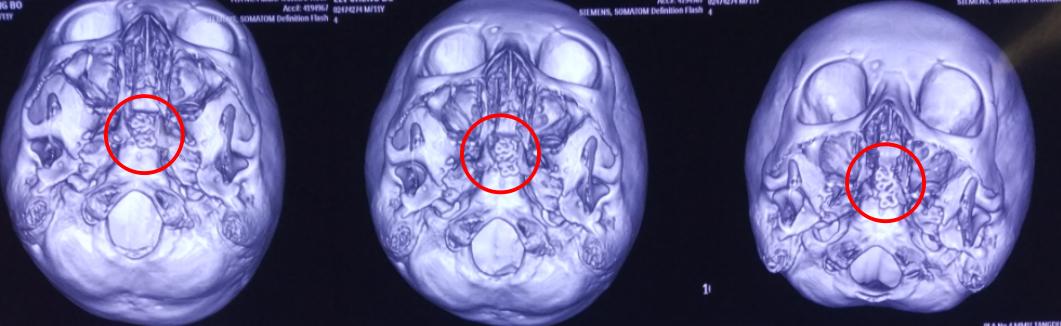

手术行“经鼻蝶脑膜脑膨出回纳并修补术”,一切顺利。术后患者恢复良好,无不适,不久出院调养。

术后影像